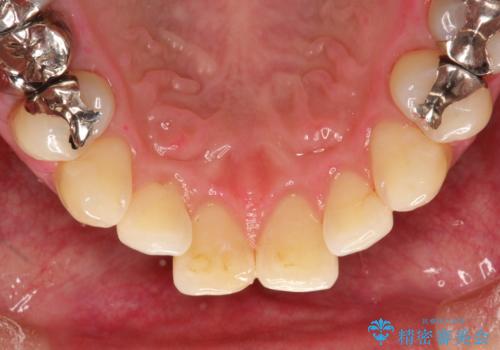

- 歯科でのクリーニングがかなり久しぶりで口臭も気になるとのことで来院されました。PMTCの60分コースで、染め出し・ブラッシング指導・クリーニングを行いました。

適切な歯磨き方法を習得するには、染め出しを行い、磨き残しを把握していくことがポイントです。

磨けているよう、磨いているつもりでも、汚れが残ってしまうと、毎日の歯磨き時間が無駄になってしまうこともあります。効率的に歯磨きを行い、磨き残しを減らせるように、歯科衛生士による専門的な指導を行います。